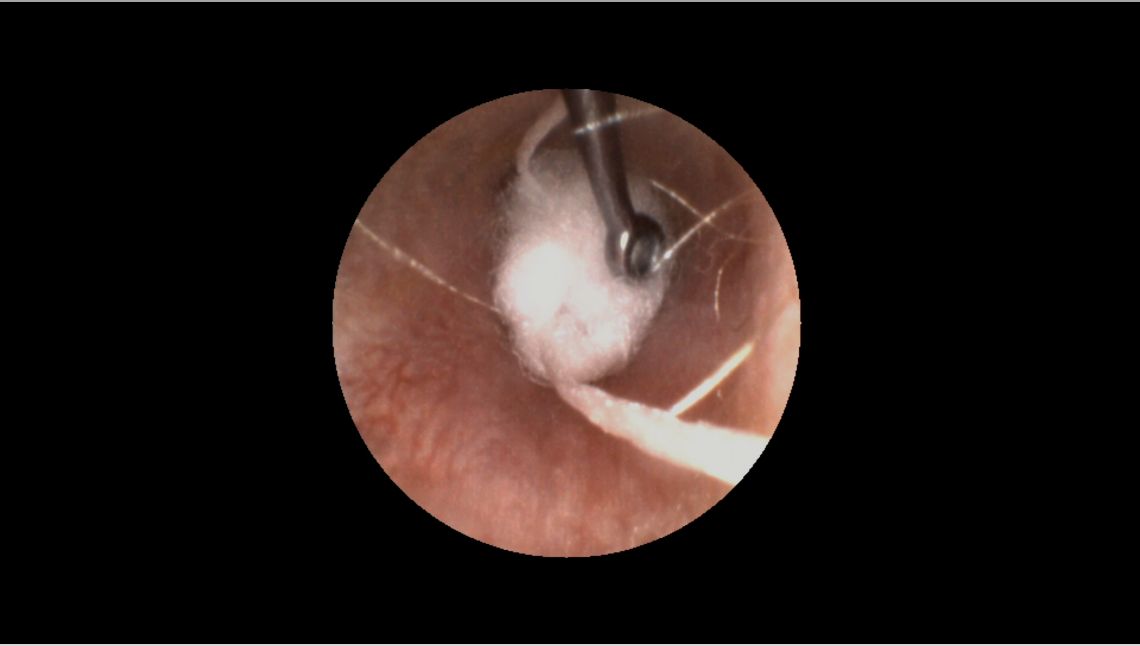

La première chose à faire est d’examiner l'oreille, de préférence avec un vidéo-otoscope.

Conseils pro : votre vidéo-otoscope est votre meilleur allié—il est l’outil indispensable lorsque vous nettoyez les oreilles, prenez les empreintes et voulez montrer ce que vous faites aux patients.